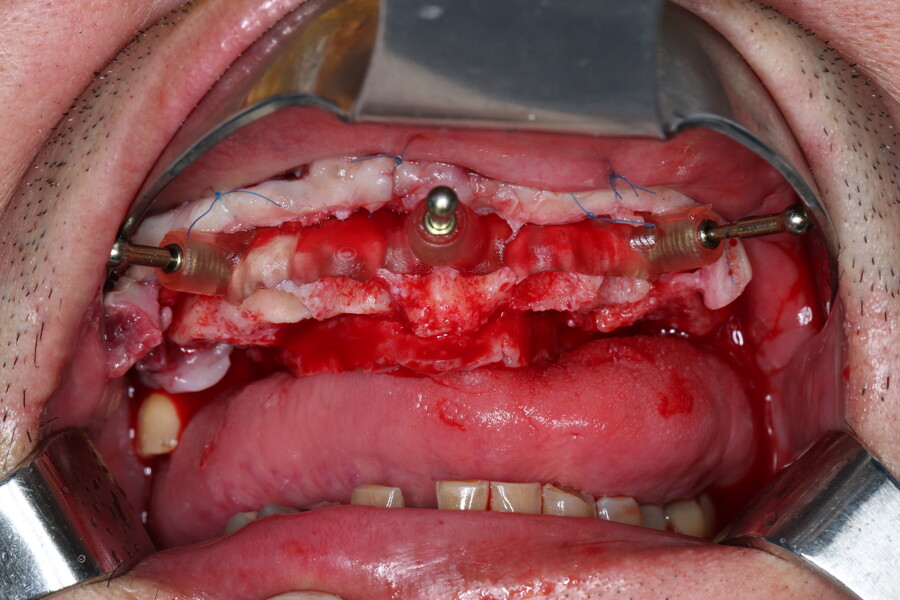

Compromised maxillary dentition treated with Straumann Pro Arch and a digital workflow